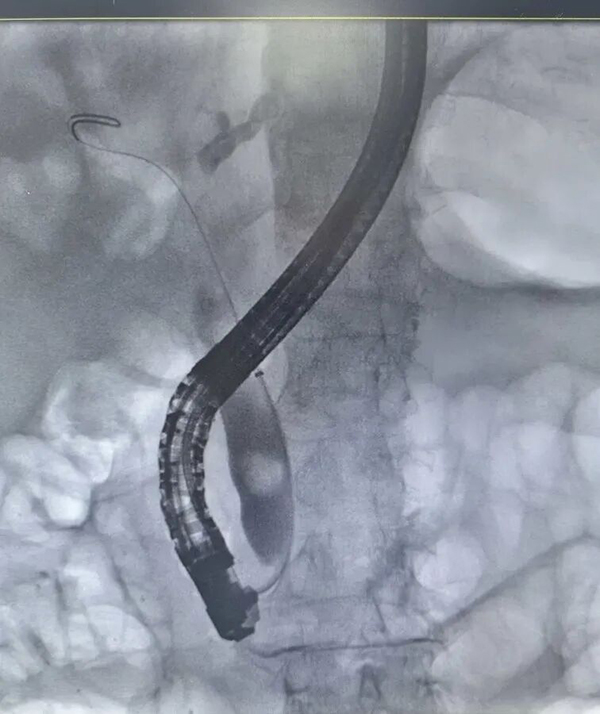

第一步:消化内科先行ERCP,解决胆总管结石。

入院后,消化内科团队为孙奶奶实施了ERCP(经内镜逆行胰胆管造影术),成功取出了胆总管结石,解除了胆道梗阻。

这一步为后续手术扫清了关键障碍,肝功能得到改善,感染风险下降,患者身体状态被调整到相对理想的水平。